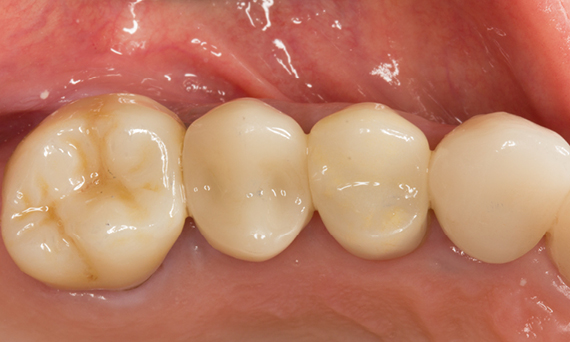

Antes: Obturaciones insuficientes en el segundo cuadrante. Las restauraciones tenían alrededor de 15 años.

Después: Coronas fabricadas chairside hechas de CEREC Tessera (dientes 26/27). Inlays para los dientes 24 y 25 hechas de bloques de composite.